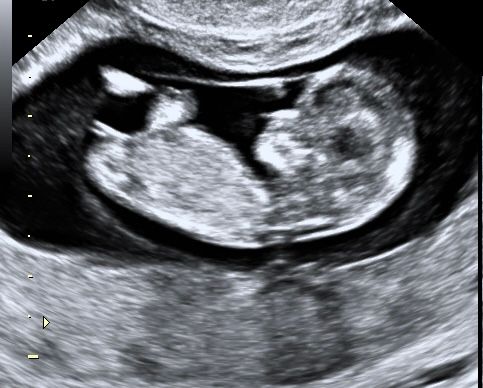

Угадайка 😁

Девочка)

Половой бугорок как у девочки

Мне кажется девочка.Слишком прямо половой бугорок

Если то,что выпирает это половой бугорок, то очень похоже на девочку, у мальчиков бугорок прям под 90градусов почти торчит, у нас на этом сроке врач предположила мальчика по половому бугорку, НИПТ подтвердил

Больше на пуповину похоже по длине😅 Но если это половой бугорок такой, то скорее девочка